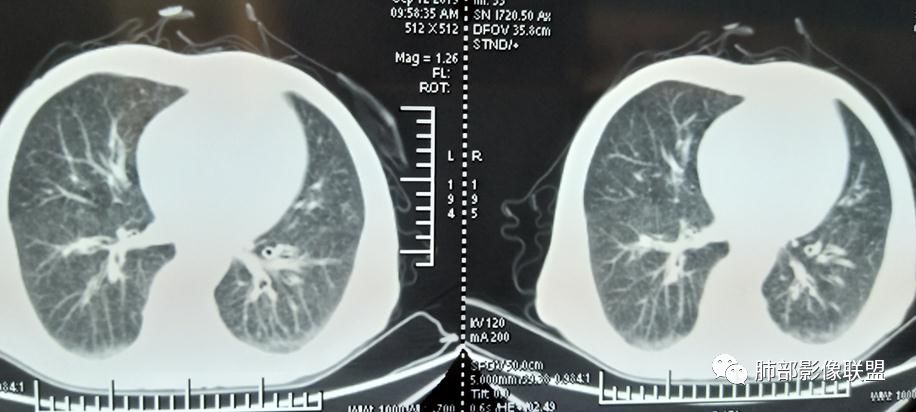

2019年9月12日CT(外院片,手机拍摄)

2019-10-20复查CT如下:

两肺弥漫性粟粒样结节伴左上肺小结节,呈三均匀分布,有结核的临床表现,支持血性播散性肺结核。

大小、分布均匀,边缘清楚

细小结节,弥漫,撒米粒样——血道来源

部分可见分支状

血道来源的病灶,均匀、细微,而且部分有分支状,都符合粟粒型肺结核

急性血行播散型肺结核  两肺广泛分布粟粒大小的结节状密度增高影,具有大小均匀、分布均匀、密度均匀的典型“三均匀”特征,注意急性血播病灶非常小,一般粟粒影直径1~2mm。

病灶密集者出现肺外围血管影不清或减少。